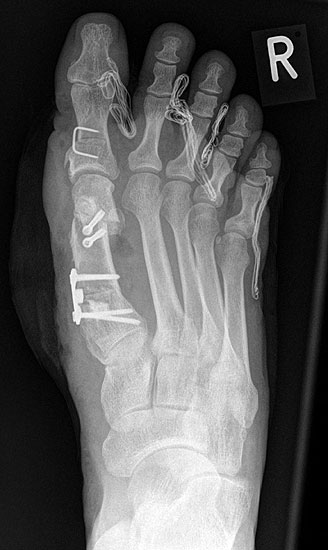

Die dorsoplantaren Röntgenaufnahmen zeigen eine Open-wedge Technik mit der normalerweise ein erhöhter intermetatarsaler Winkel gut zu korrigieren ist (Abbildung 3). Die Wirksamkeit einer Basisosteotomie ist umso größer, je proximaler diese durchgeführt wird. Je weiter distal die Osteotomie, umso geringer die Korrektur. Auf den postoperativen Bildern ist der distal unverändert große Abstand zwischen Metatarsale I und Metatarsale II erkennbar, bei gleichzeitiger Subluxation des Großzehengrundgelenks und dezentrierten Sesambeinen. Darüber hinaus finden sich initiale degenerative Veränderungen im Großzehengrundgelenk. Klinisch bestand eine hohe Weichteilspannung, bei verkürzter Extensor- und Flexor hallucis longus Sehne.  Daher wurde ein verkürzendes Verfahren zur Revision gewählt (Abbildung 4). Die Lapidusarthrodese stellt ein sehr zuverlässiges Verfahren zur Behandlung von Hallux valgus Rezidiven dar 9. Die Fusion des Tarsometatarsale-I-Gelenks kombiniert Stabilität mit einem hohen Korrekturpotenzial. Aufgrund der verfahrensimmanenten Verkürzung des ersten Strahls und der in diesem Fall bereits präoperativ vorhandenen Transfermetatarsalgie wurde die Entscheidung für eine verkürzte Weil-Osteotomie am zweiten bis fünften Strahl gefällt. Die Kombination beider Verfahren führte zu einem homogenen Metatarsale-Index und zu einer gleichmäßigen plantaren Druckverteilung 10. Die Hallux valgus interphalangeus Fehlstellung wurde mit einer Akin-Osteotomie korrigiert.